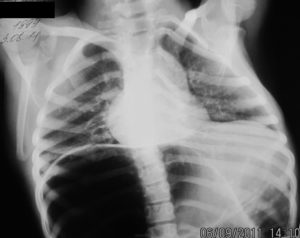

Диагностика грыжи пищевода включает использование различных методов, таких как рентген, УЗИ и фиброгастроскопия. Гастроэнтеролог и хирург общей практики проводят обследование пациента, чтобы поставить диагноз «грыжа пищеводного отверстия». Для дифференциальной диагностики используются следующие методы:

Рентген с использованием контрастного вещества сульфата бария, которое вводится через рот. Этот метод позволяет оценить функциональные свойства пищевода и других органов ЖКТ, включая перистальтику.

УЗИ — общий осмотр внутренних органов грудной и брюшной полости. Этот метод позволяет увидеть и определить то, что не может быть обнаружено при рентгене.